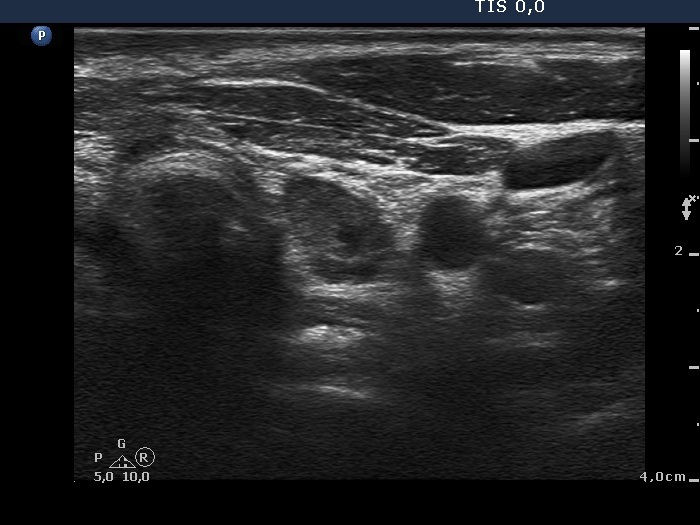

Ultrasonography: The thyroid was echonormal. There were several hypoechogenic nodules presenting microcalcifications in both lobes and in the isthmus. There was a similar lesion under the lower pole of the left lobe. The vascularization of the lesions was variable.

Ultrasonography. There was no parenchyma according to the right thyroid bed. There were two hypoechogenic lesions in the lower pole of the left thyroid bed. Both were irregular in shape and presented cystic degeneration and microcalcifications. There was a reactive-type lymph node ventral to the previously described lesions.